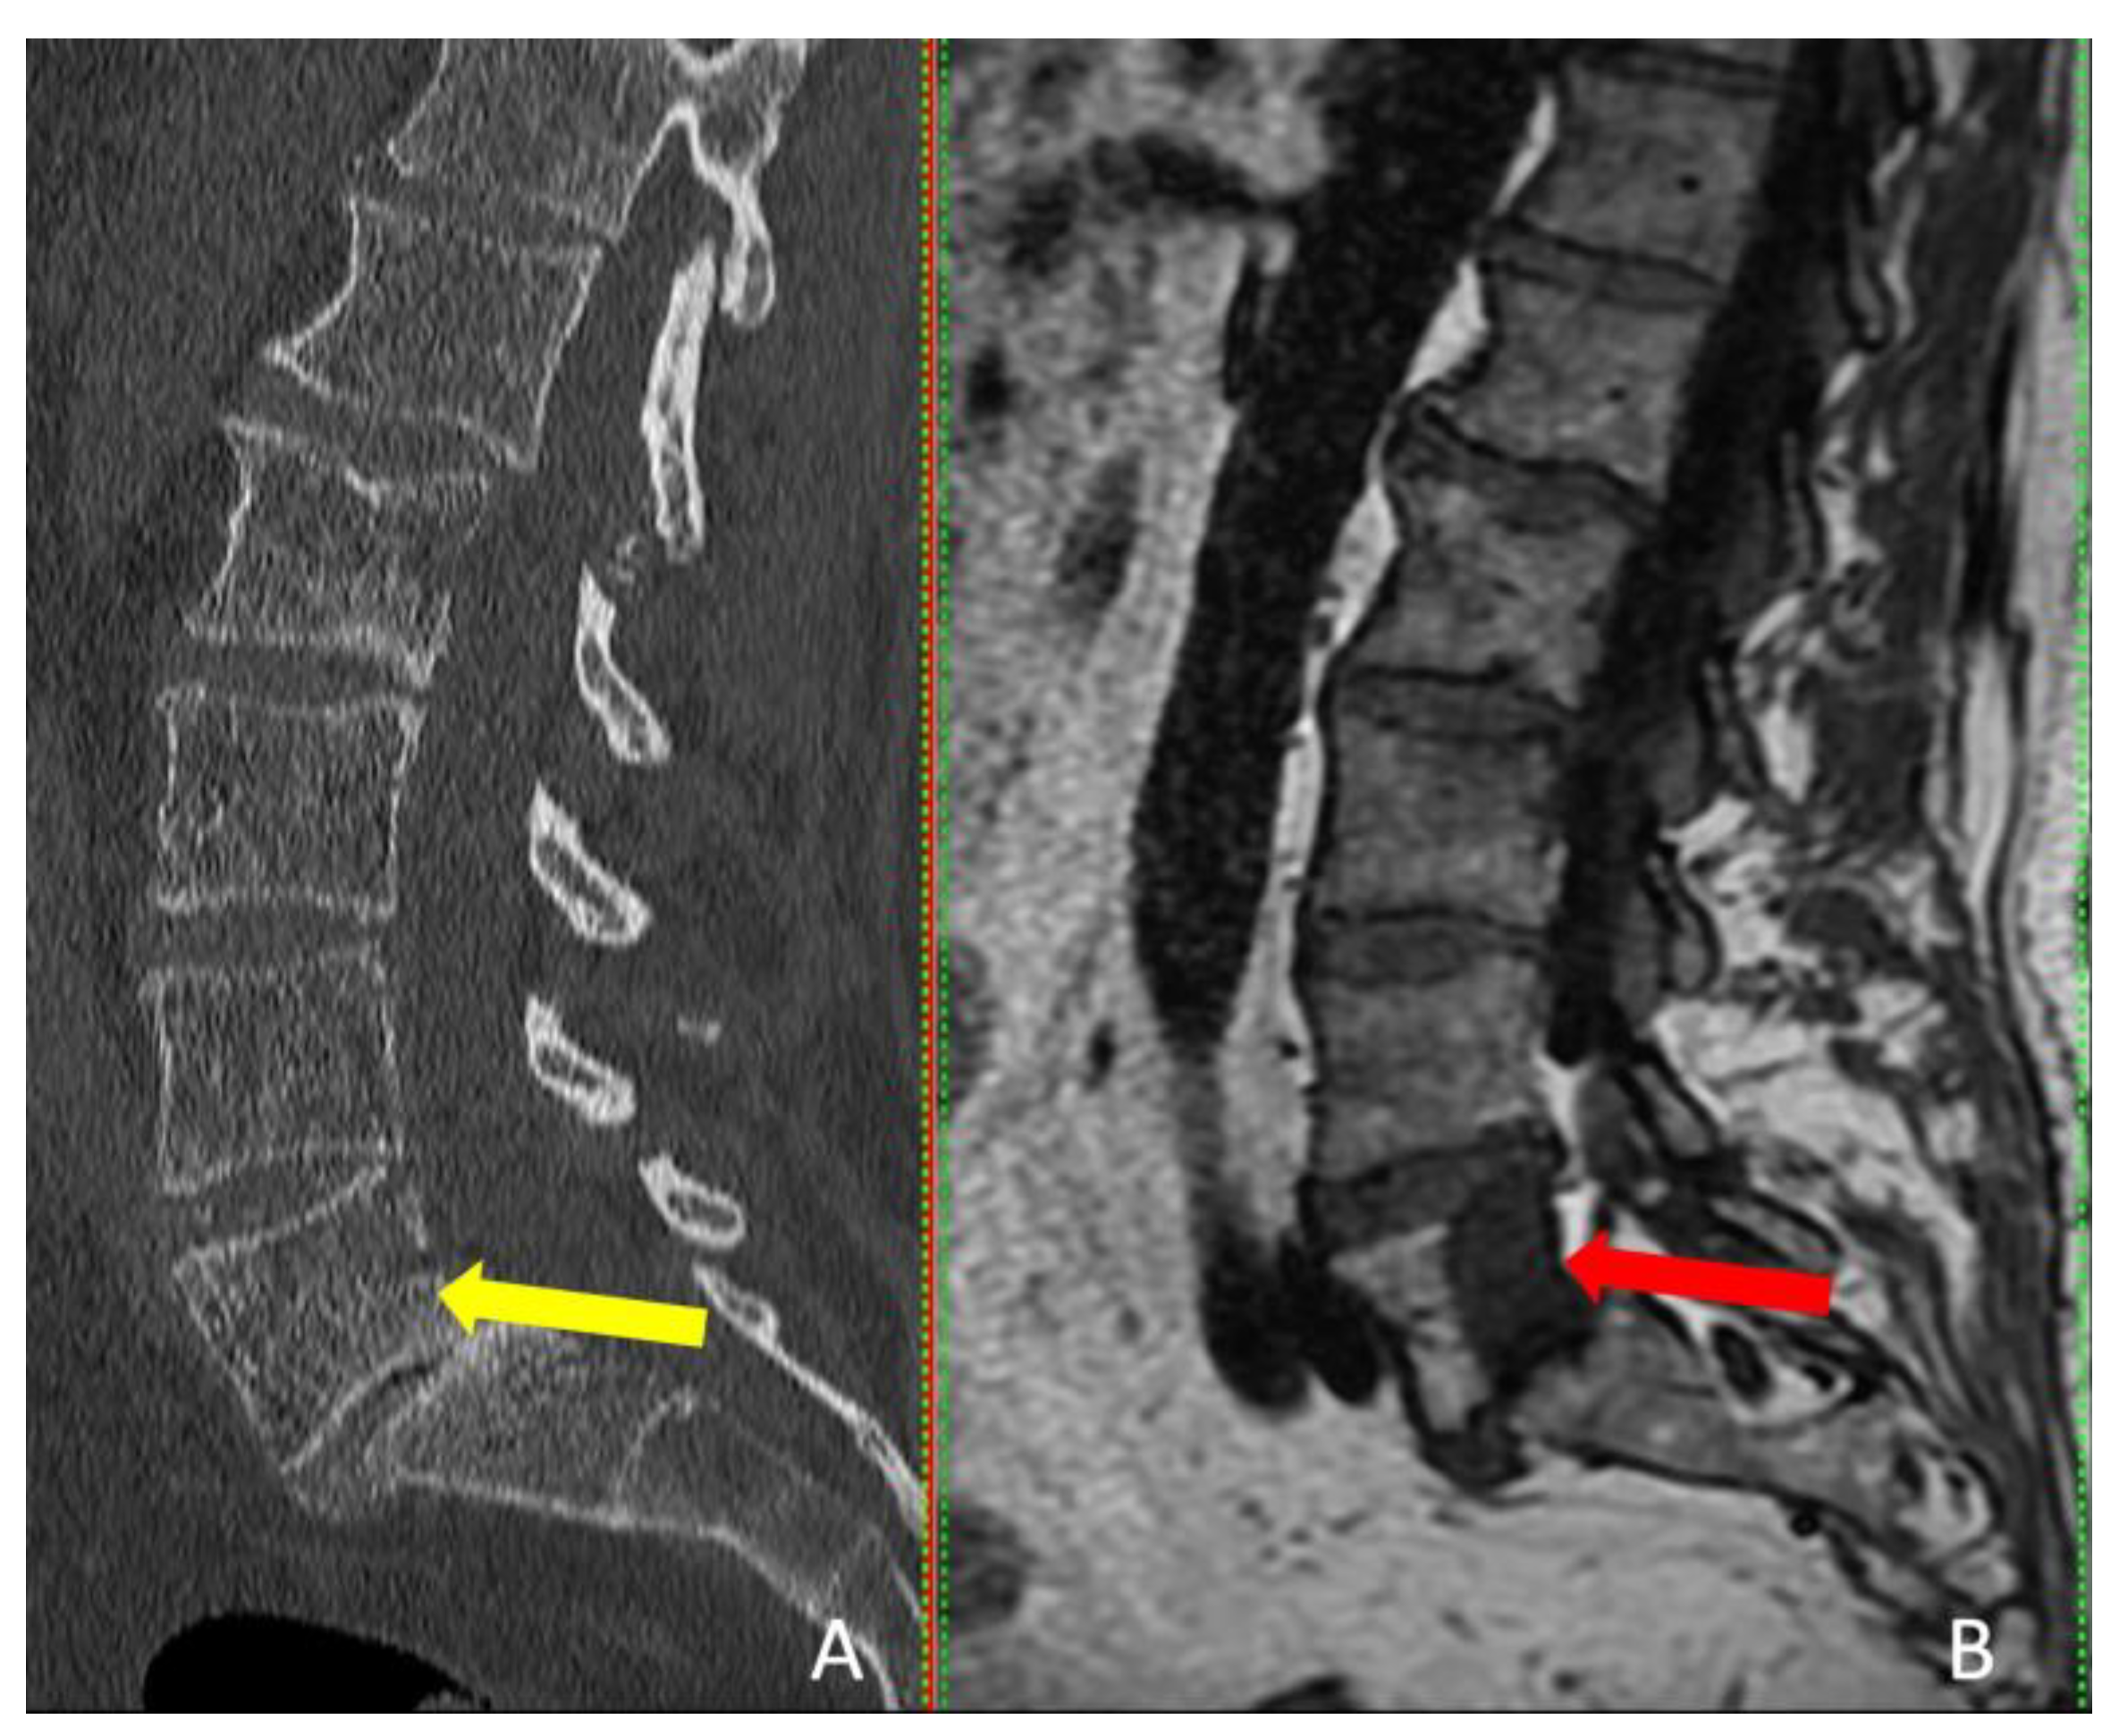

Interestingly, the tumor was visible on CT in only one patient, but MRI provided more accurate tumor dimensions (Table 2). MRI successfully revealed the tumors in all four patients (Figure 4). These patients presented with localized pain that did not radiate to the legs.

To accurately detect and target tumors to undergo ablation, it is essential to address the limitations of each imaging technique. While CT scans are often recommended for hard to reach lesions due to their high-resolution capabilities, which are particularly useful for visualizing the sides of vertebrae and thus minimizing the risk to neural elements (37), MRI excels in soft-tissue and bone marrow contrast and certain lesions such as non-Hodgkin's lymphoma, can only be visualized using MRI (14,38,39). A study by Al-Smadi et al. involving 18 patients with spinal column tumors revealed that the tumors were either not visible or their dimensions were underestimated when relying solely on CT scans, as opposed to MRI (19).

Figure 4. Sagittal view of CT scan (A), and MRI scan (B). The red arrow indicates the tumor, and the yellow arrow shows where the tumor should be detectable.